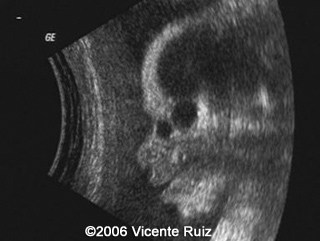

This is a case of dacryocystocele in a third  trimester fetus. Note the cystic mass between the right medial cantus and the nose.